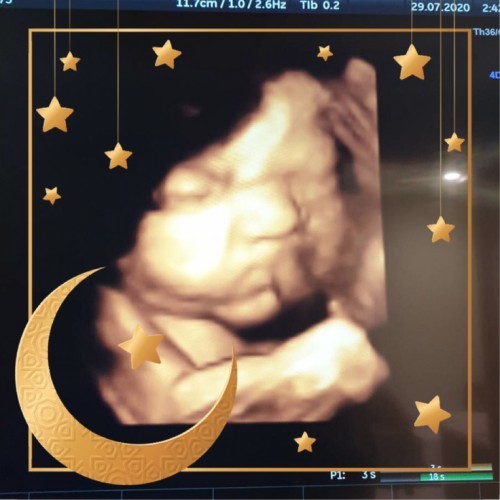

เอารูปอัลตร้าชาวแม่ๆตอนนี้มาอวดกันหน่อยคะกี่วีคแล้วคลอดวันไหนกันมั้งเราคลอด26มกราคะ